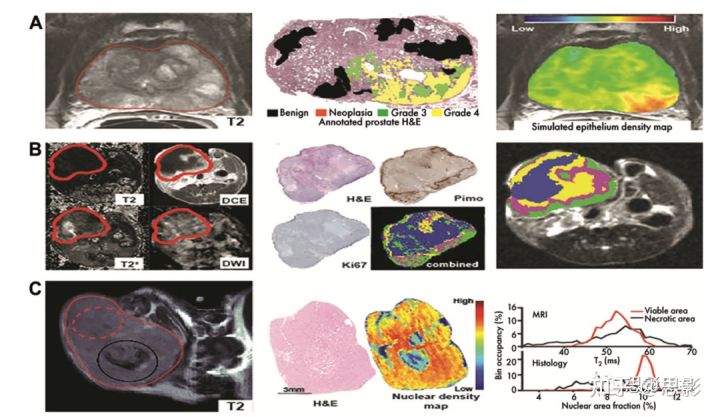

图4:结合组织学提供对图像特征的生物学见解。

A、McGarry等人利用多参数MRI信息(左)构建了模型,并在联合配准的带注释的苏木精-伊红染色玻片(中)上训练,以模拟前列腺上皮密度(右),与肿瘤分期相关。

B、Jardim Perassi使用多参数MRI(左),并与生存率、增殖和缺氧的组织学图(中)进行结合,以了解其生物学意义(右)。

C、Tomaszewski等人提出了T2加权MRI(左)直方图放射治疗反应的生物标志物,并使用组织学衍生核密度图(中)通过直方图特征的相似性来证明观察到的影像变化(右)。

已经提出了其他方法来克服这一局限性,方法是在与活体成像相匹配的空间尺度上关注组织病理学信息。Bobholz等人(78)共同采集了MRI和苏木精-伊红染色的组织学图像,这些图像被降采样到MRI分辨率,以比较两个数据集中的局部纹理信息。通过比较图像匹配区域的影像组学特征,确定了两种模式之间密切相关的特征。虽然没有直接揭示这些特征的生物学基础,但这些发现使我们更接近一个解决方案,因为苏木精-伊红染色模式的生物学意义比大多数MRI扫描更明确。此外,还应了解低分辨率影像特征和病理特征之间的密切相关性。McGarry等人(79,80)描述了这一方向的一个步骤,再次使用苏木精-伊红染色和多参数MRI数据集,对前列腺癌中与肿瘤分级相关的组织学参数进行局部影像组学预测,尽管该模型的无监督性质并未揭示不同多参数MRI模态对预测的直接贡献。T omaszewski等人(81)也使用MRI和病理图像的量化特征来验证治疗反应。这些示例说明了体内和体外图像的结合对于深入了解关系的详细空间分辨率的价值,如图4所示。这些发现的局部性质并不能总是直接转化为影像组学分析的主要目的,影像组学分析侧重于患者生存和反应的一般特征。然而,局部比较和观察到特征的相关性可以阐明影像组学指标的生物学意义,并可以为观察到的结果特征提供额外的验证,从而能够筛选与组织学发现相关的特征。